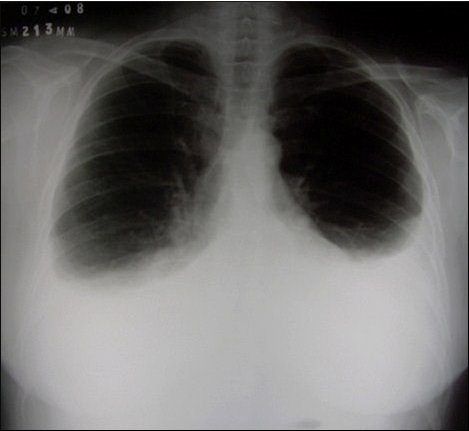

Rx de torax em 07/04/2008 evidencia imagem de hipotransparência em terço inferior de campos pleuropulmonares bilaterais, do tipo derrame pleural.